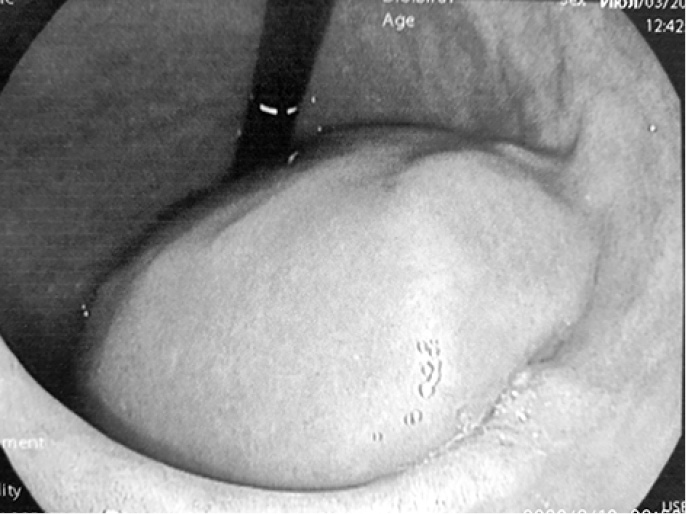

С диагнозом: «Tumor брюшной полости» поступил 02.07.2019 г. в хирургическое отделение КГБУЗ «Городская больница № 5 г. Барнаула», где провели уточняющую диагностику – эндоультрасонография от 03.07.2019 г. Видеогастроскоп проведён в желудок. Стенки желудка хорошо расправляются воздухом. В просвете желудка на большой кривизне дистальной части тела желудка на 2/3 шаровидное эластичное выбухание с подвижной гиперемированной слизистой оболочкой диаметром до 70 мм (рис. 5–7), эндосонограф свободно проведён. Сканирование в режиме 7,5–10,0 МГц. Полостное жидкостное образование диаметром 63 мм, пристеночно содержит гипоэхогенную ткань толщиной местами до 15 мм. Капсула гиперэхогенная до 1,4 мм. ЦДК (-). Образование расположено в подслизистом слое. Чётко прослеживается мышечный слой за её пределами (рис. 8, 9). Между желудком и печенью гипоэхогенная ткань с наличием сосудов и анэхогенной полостью до 10 мм (рис. 10).

Рис. 5. Подслизистое образование тела желудка

Рис. 6. Подслизистое образование тела желудка

Рис. 7. Подслизистое образование тела желудка